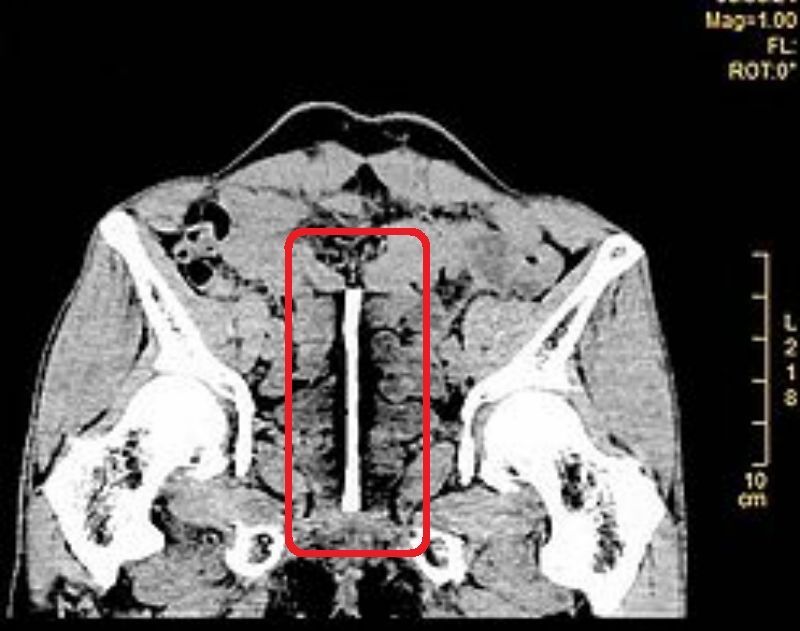

【中国】ペニスを大きくしたい為に尿道に13センチの鉄の棒を刺した男性

自分のペニスに自信が無い52歳の「Kang Niu」さん。何を思いたったのか自分のペニスに13センチの鉄の棒を入れたとの事です。